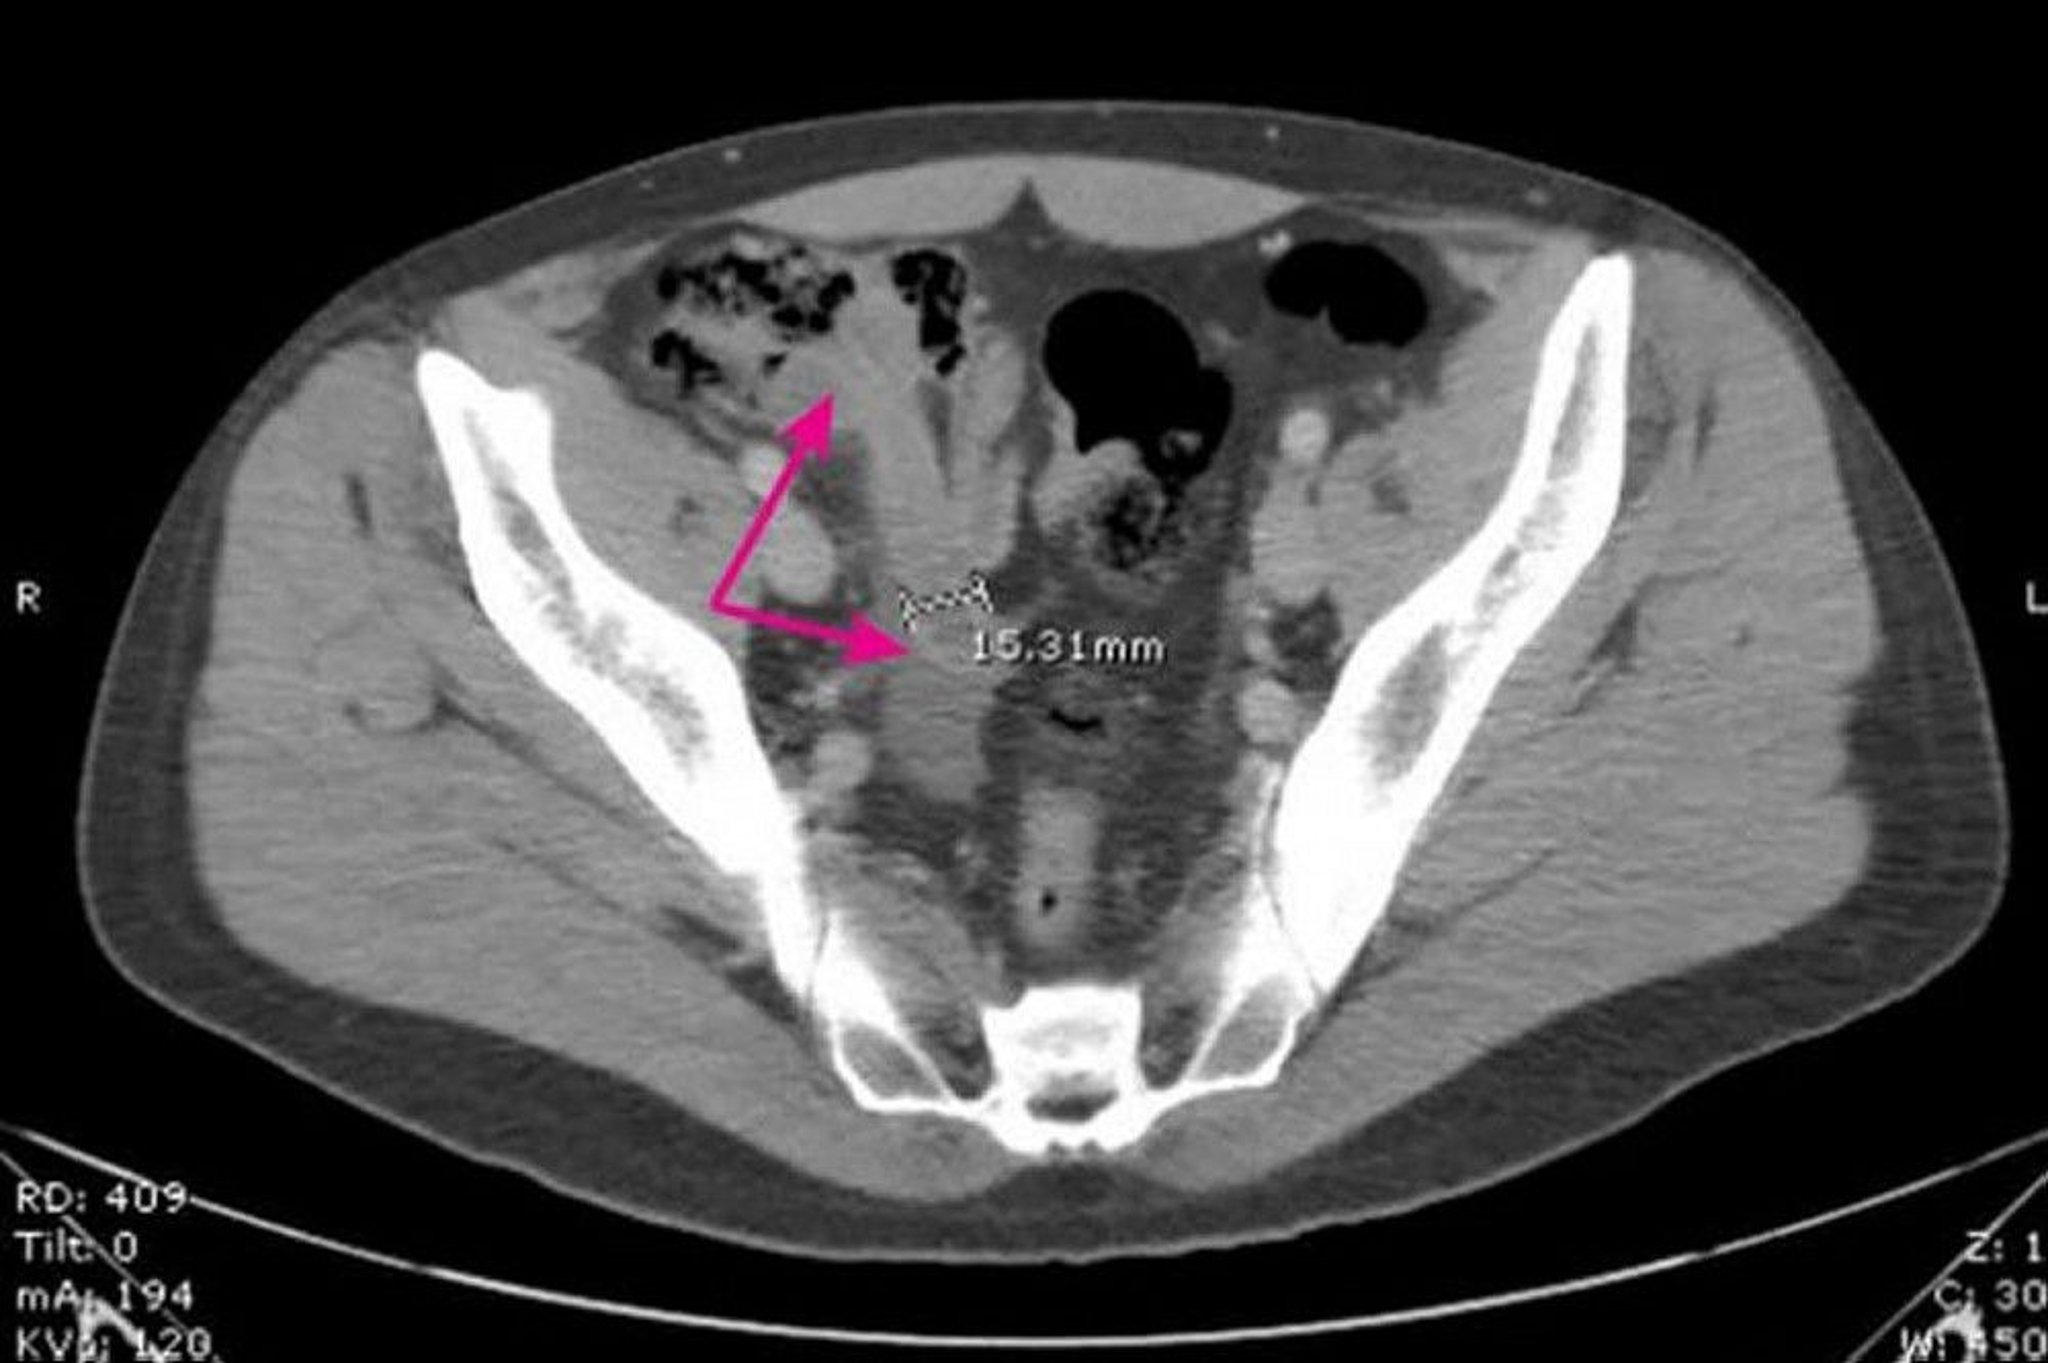

This image shows a dilated, thick-walled appendix (arrows) measuring 15.31 mm in diameter with surrounding inflammatory changes.

Image provided by Parswa Ansari, MD.